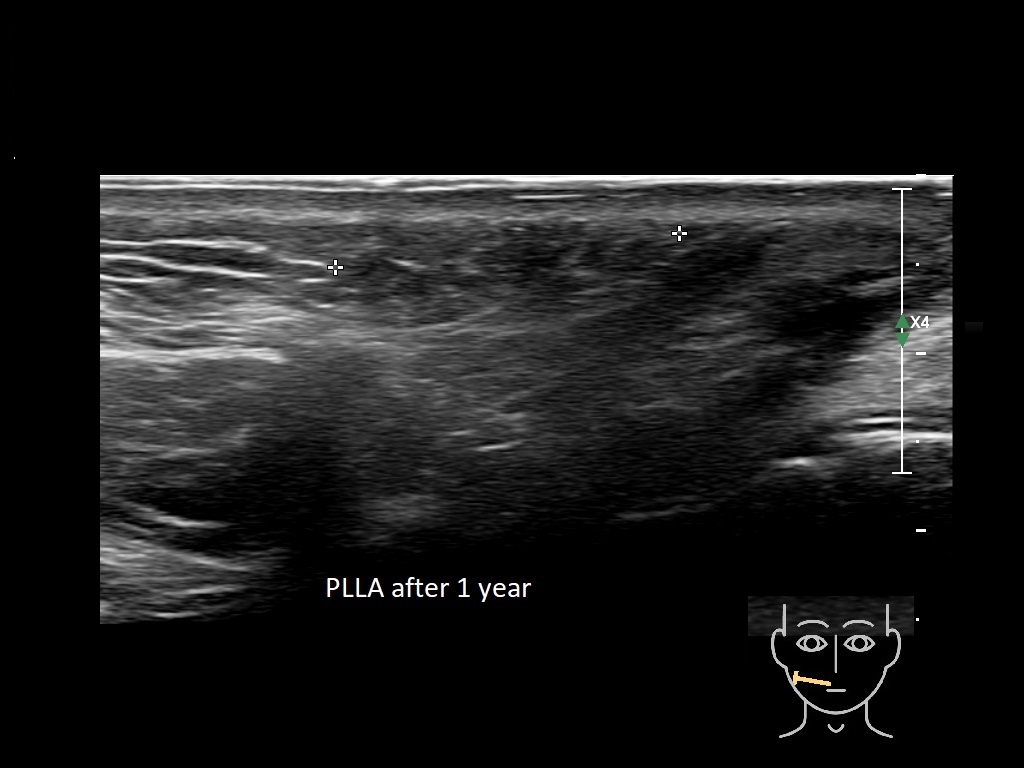

Draw in the image on the right where the fillers are located. To check if your answer is correct, please click on the secondary image.